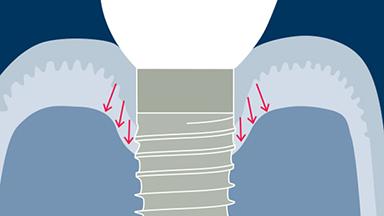

- descrever como os biofilmes microbianos se formam nos implantes e levam à inflamação do tecido mole peri-implantar e do osso de suporte

- identificar os efeitos da inflamação nos tecidos moles peri-implantares e no osso de suporte

- listar os parâmetros clínicos necessários para monitorar a saúde do tecido mole peri-implantar e do osso de suporte